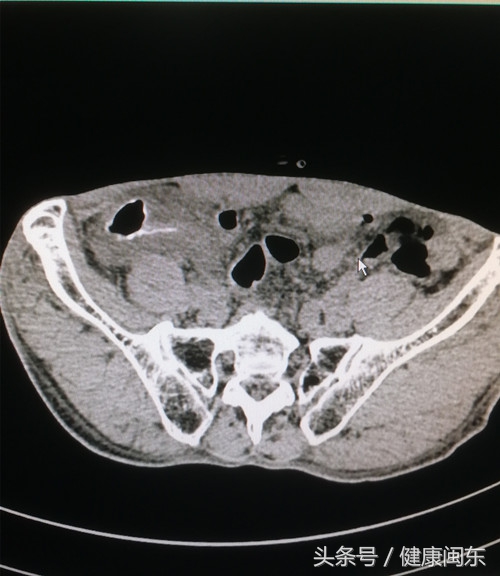

马先生入院后,心胸普儿外科医生经完善各项检查,显示有右下腹回盲部肠壁稍肿胀,经输液保守治疗无效,张清华副主任医师当机立断进行腹腔镜探查,手术中看见的情况是:回盲部穿孔,直径1厘米,阑尾炎症。术后送病理检查显示:急性化脓性阑尾炎伴穿孔,阑尾周围炎,并见虫卵性钙化;肠粘膜急性化脓性炎症。元凶原来是寄居马先生体内的寄生虫,成虫将卵产致粘膜下方,大量虫卵沉积于微血管内,宿主对虫卵的炎症和纤维化反应,进而发展成为穿孔所致。

“几经周折,终捉拿凶手‘血吸虫’” 张清华副主任医师说道,血吸虫病的主要病变是由虫卵引起肝脏和肠道的肉芽肿形成,病理检查是诊断血吸虫病的重要方法之一。各阶段的虫体均可对人体产生一定程度的损伤,尾蚴、童虫和成虫所致的损伤多为一过性或较轻微,而沉积于微血管内的大量虫卵以及宿主对虫卵的炎症和纤维化反应为血吸虫病的主要病理基础。